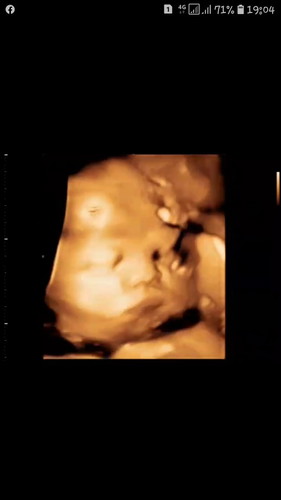

34weekเองครับ

ผมอายุได้34week??น้ำหนักแค่2667g☺☺เกินมานิดๆหน่อยๆป้าหมอสั่งเบรคเรื่องกินของแม่ทันที ผมนี้งงเลยคับ??